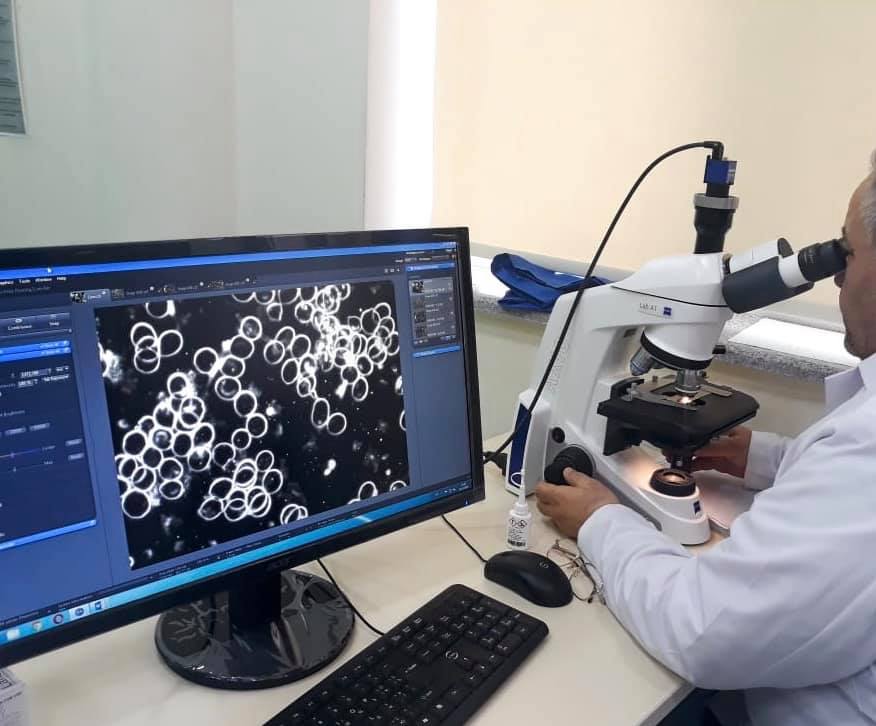

Masallı Bioloji Təbabət klinikasında çoxprofilli cərrahiyyə kabinetləri, 28 çarpayılıq palatalar, tam avtomatlaşdırılmış, müasir avadanlıqlarla təchiz olunmuş laboratoriya, geniş profilli müasir cihazlarla təchiz olunmuş fizioterapiya şöbəsi, MRT (maqnit rezonans tomoqrafiya), KT (komputer tomoqrafiyası), Rəqəmsal rentgen, Panoram rentgen, qastroendoskop, USM və s. diaqnostik cihazlar quraşdırılmışdır. Bundan əlavə, müalicəvi sanatoriya xidməti göstərmək üçün Naftalan palçıq vannaları, Naxçıvan duzundan yaradılmış "aspiratorlu Duz mağarası” bölgə əhalisinin istifadəsinə verilmişdir.